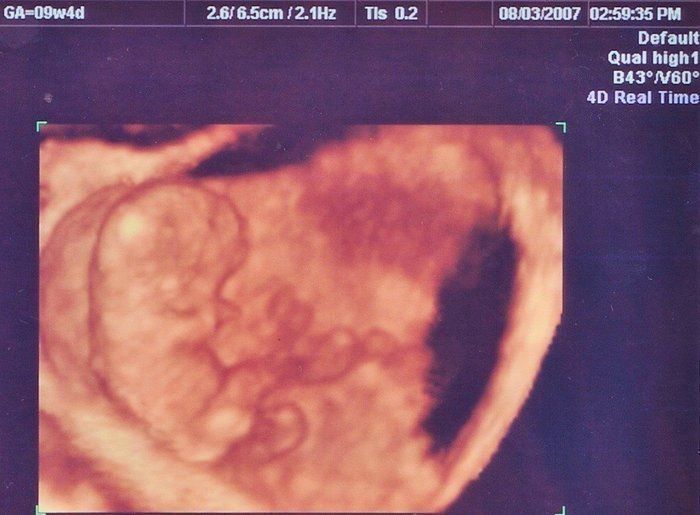

クリコさんの妊娠9週目のエコー写真

4D画像で頭、手、足を見ることができました。枝豆のような頭の形でなんだかかわいい、と早くも親バカ。この時期は、子宮がんや感染症の免疫の有無など、様々な検査を行いました。実母に、私がはしかやおたふく風邪にかかったかなどや、母がどのような妊娠・出産をしたかを教えてもらいました。